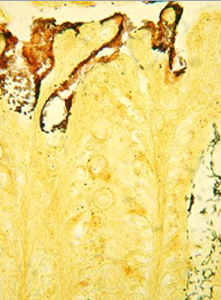

研究者将柠檬酸杆菌引入小鼠肠道中,两个月后就可以在小鼠肠道中的多个位点发现不同水平的柠檬酸杆菌,这种新型计算机算法可以帮助研究人员在和感染、炎症相关的肠道复杂菌群中鉴别出细菌的动力学改变。

当小鼠处于感染期间时,研究者在小鼠肠道的不同位置发现了正常菌群的许多破坏情况,比如,研究人员发现小鼠结肠组织中的细菌标记在小鼠感染细菌后出现症状之前的水平不断下降,而其它的标记包括梭菌和乳杆菌家族的水平出现了上升的趋势;更有意思的是,这些标记中的一部分会在肠道感染病原体的位点中发生,其并不会直接损伤宿主的细胞。